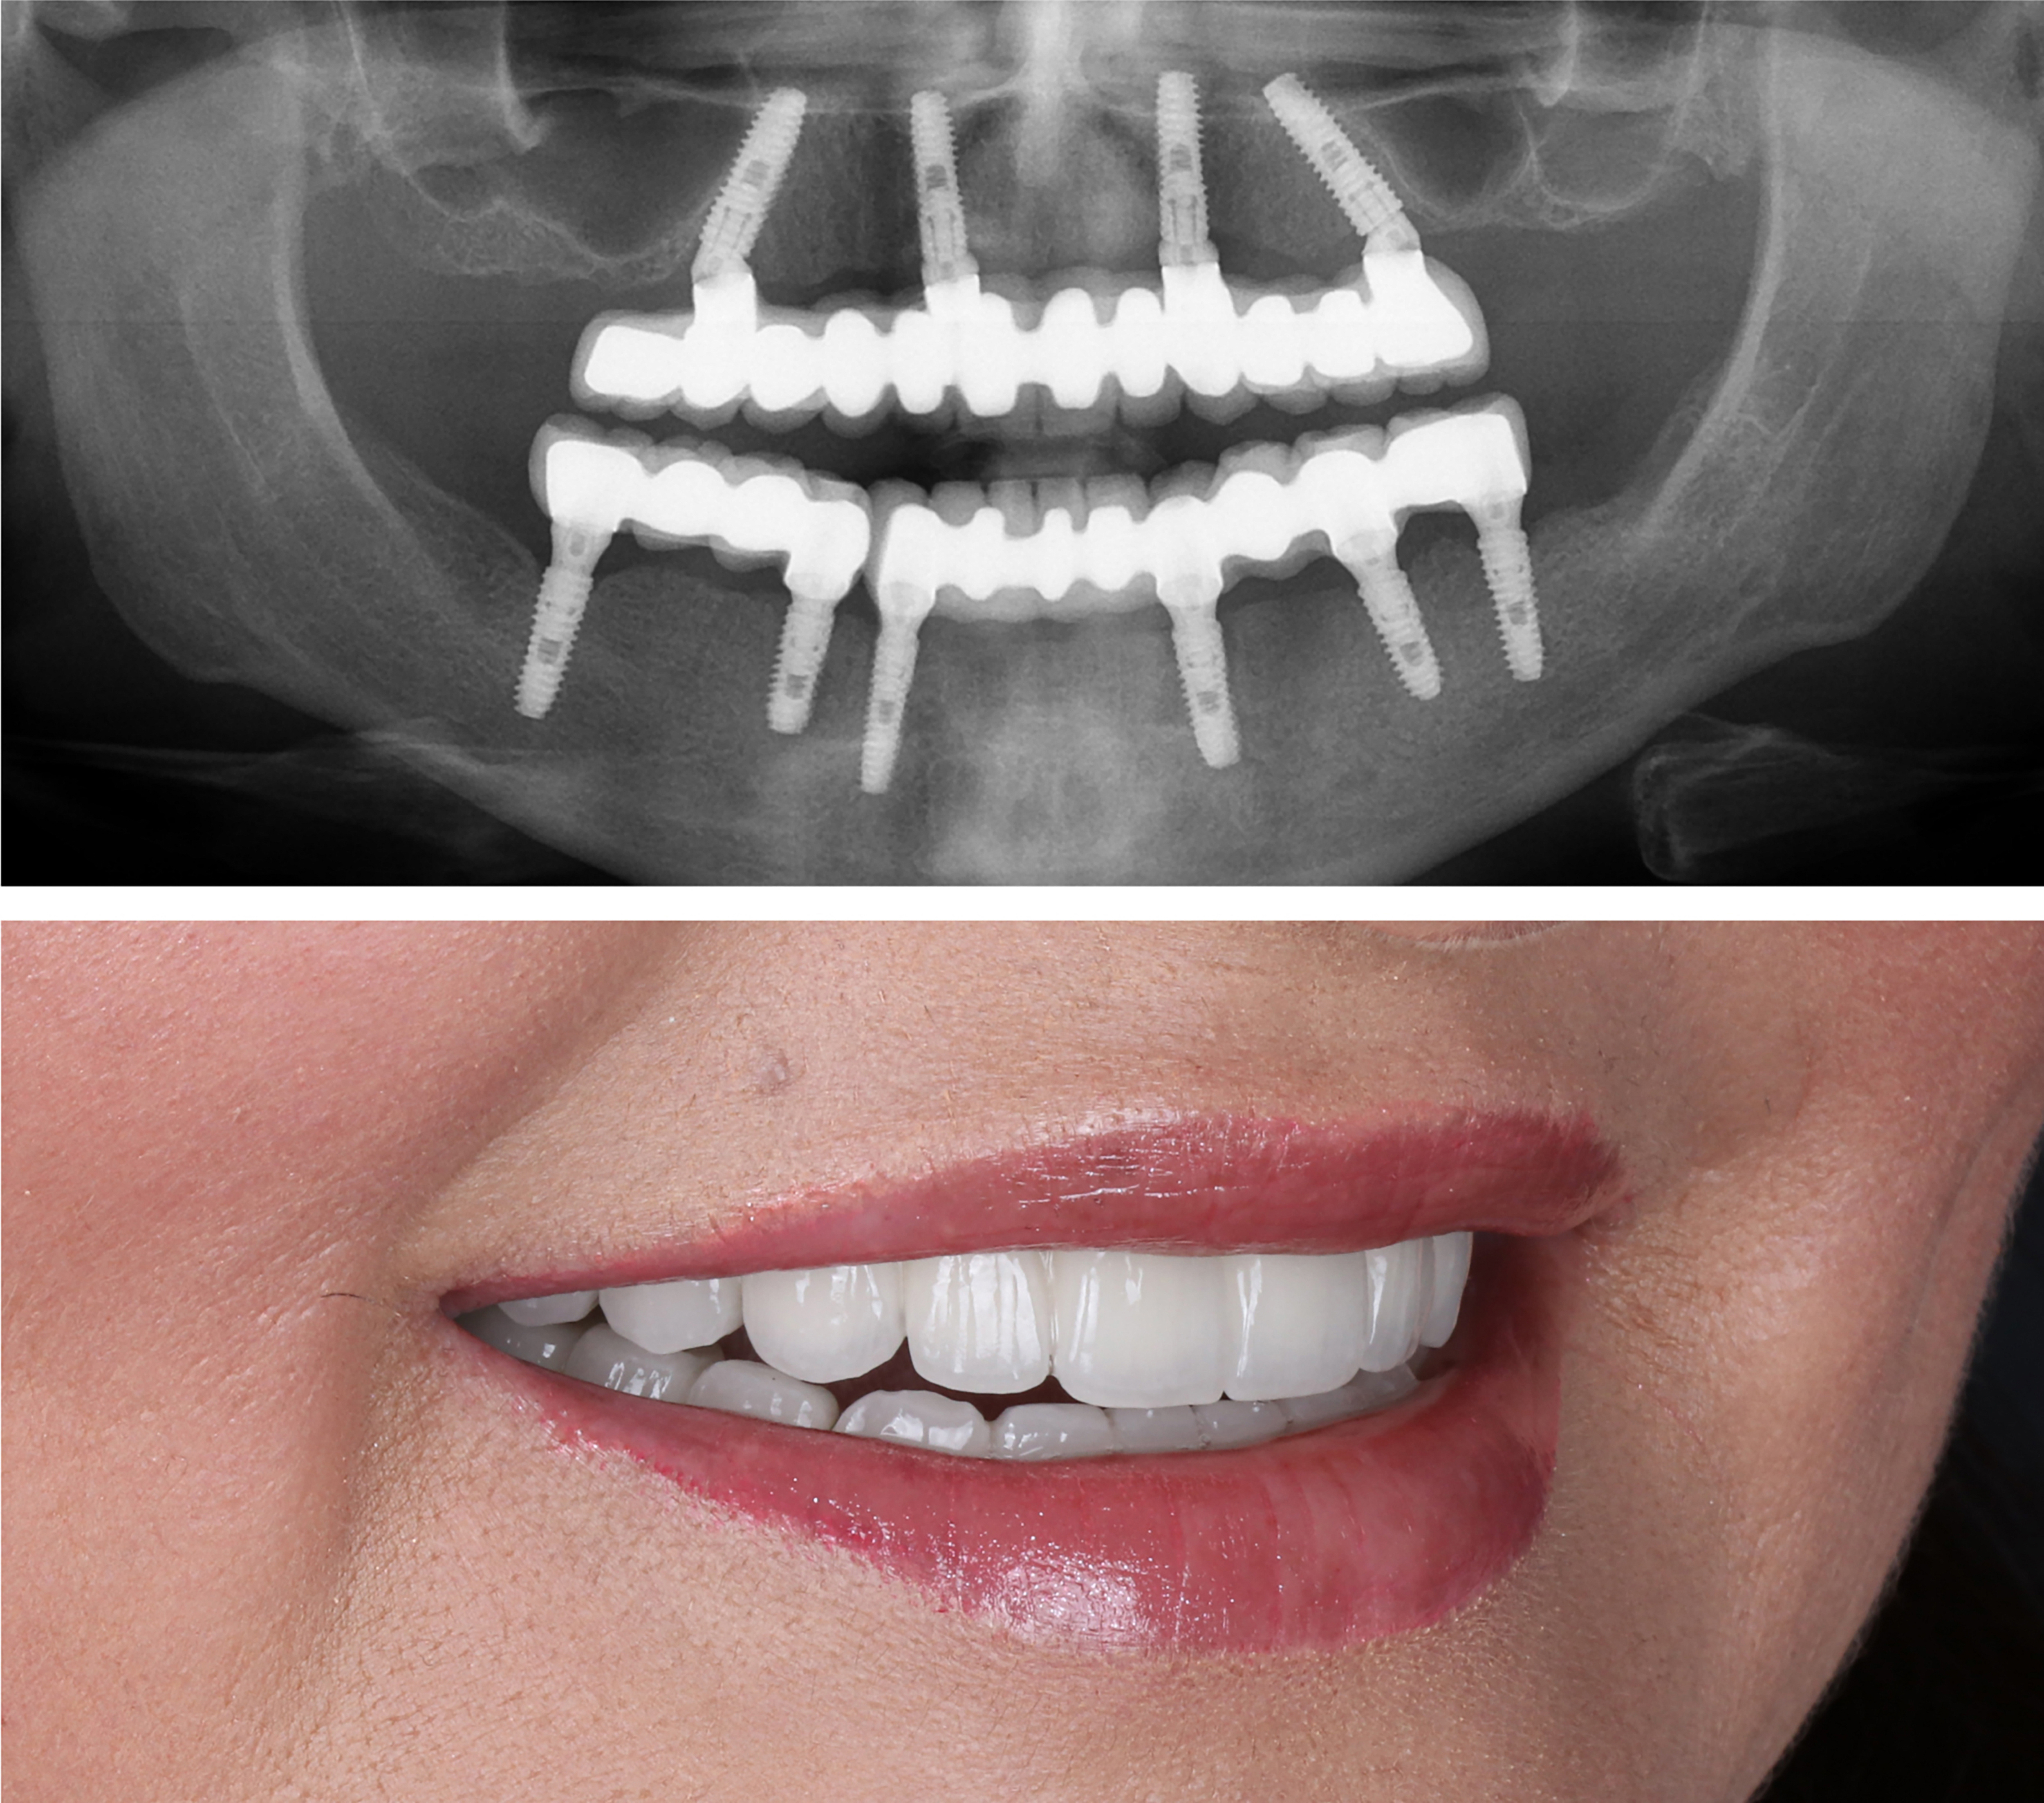

Example transformations achievable with dental implants

Every single dental implant consists of three parts - the implant, the abutment, & the crown. The implant is made of medical grade titanium. This part is surgically placed into the patient’s jaw bone and left to heal for 4-6 months afterwards.

This implant piece acts as the foundation for the rest of the tooth. Once the bone around the site has healed, the abutment and crown are placed on top of the implant. The end result is a beautiful, natural-looking new tooth!

Few people will ever be able to tell the difference between your implants and your real teeth.